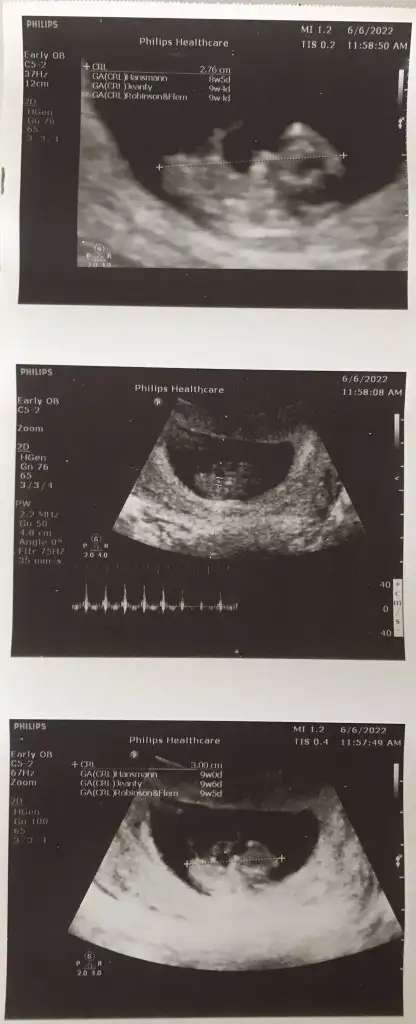

5 ve 14. haftaya kadar olan ultrason fotolarınızı paylaşın. Vajinadan mı yoksa karından mı çekildiğini ve kaç haftalık olduğunu da mutlaka belirtin.

iki kere ne dedim bilmiyorum ama bu görüntü paşa gibi9+5 karından usg2 kez aynı tahmini yaptın canım 20 gün sonra doktor tahminde bulunacakmış sen ne görüyosun hala aynı mı merak ettim

3.seferdir aynı şeyi söylüyorsun kuzum bakalımiki kere ne dedim bilmiyorum ama bu görüntü paşa gibi![]()